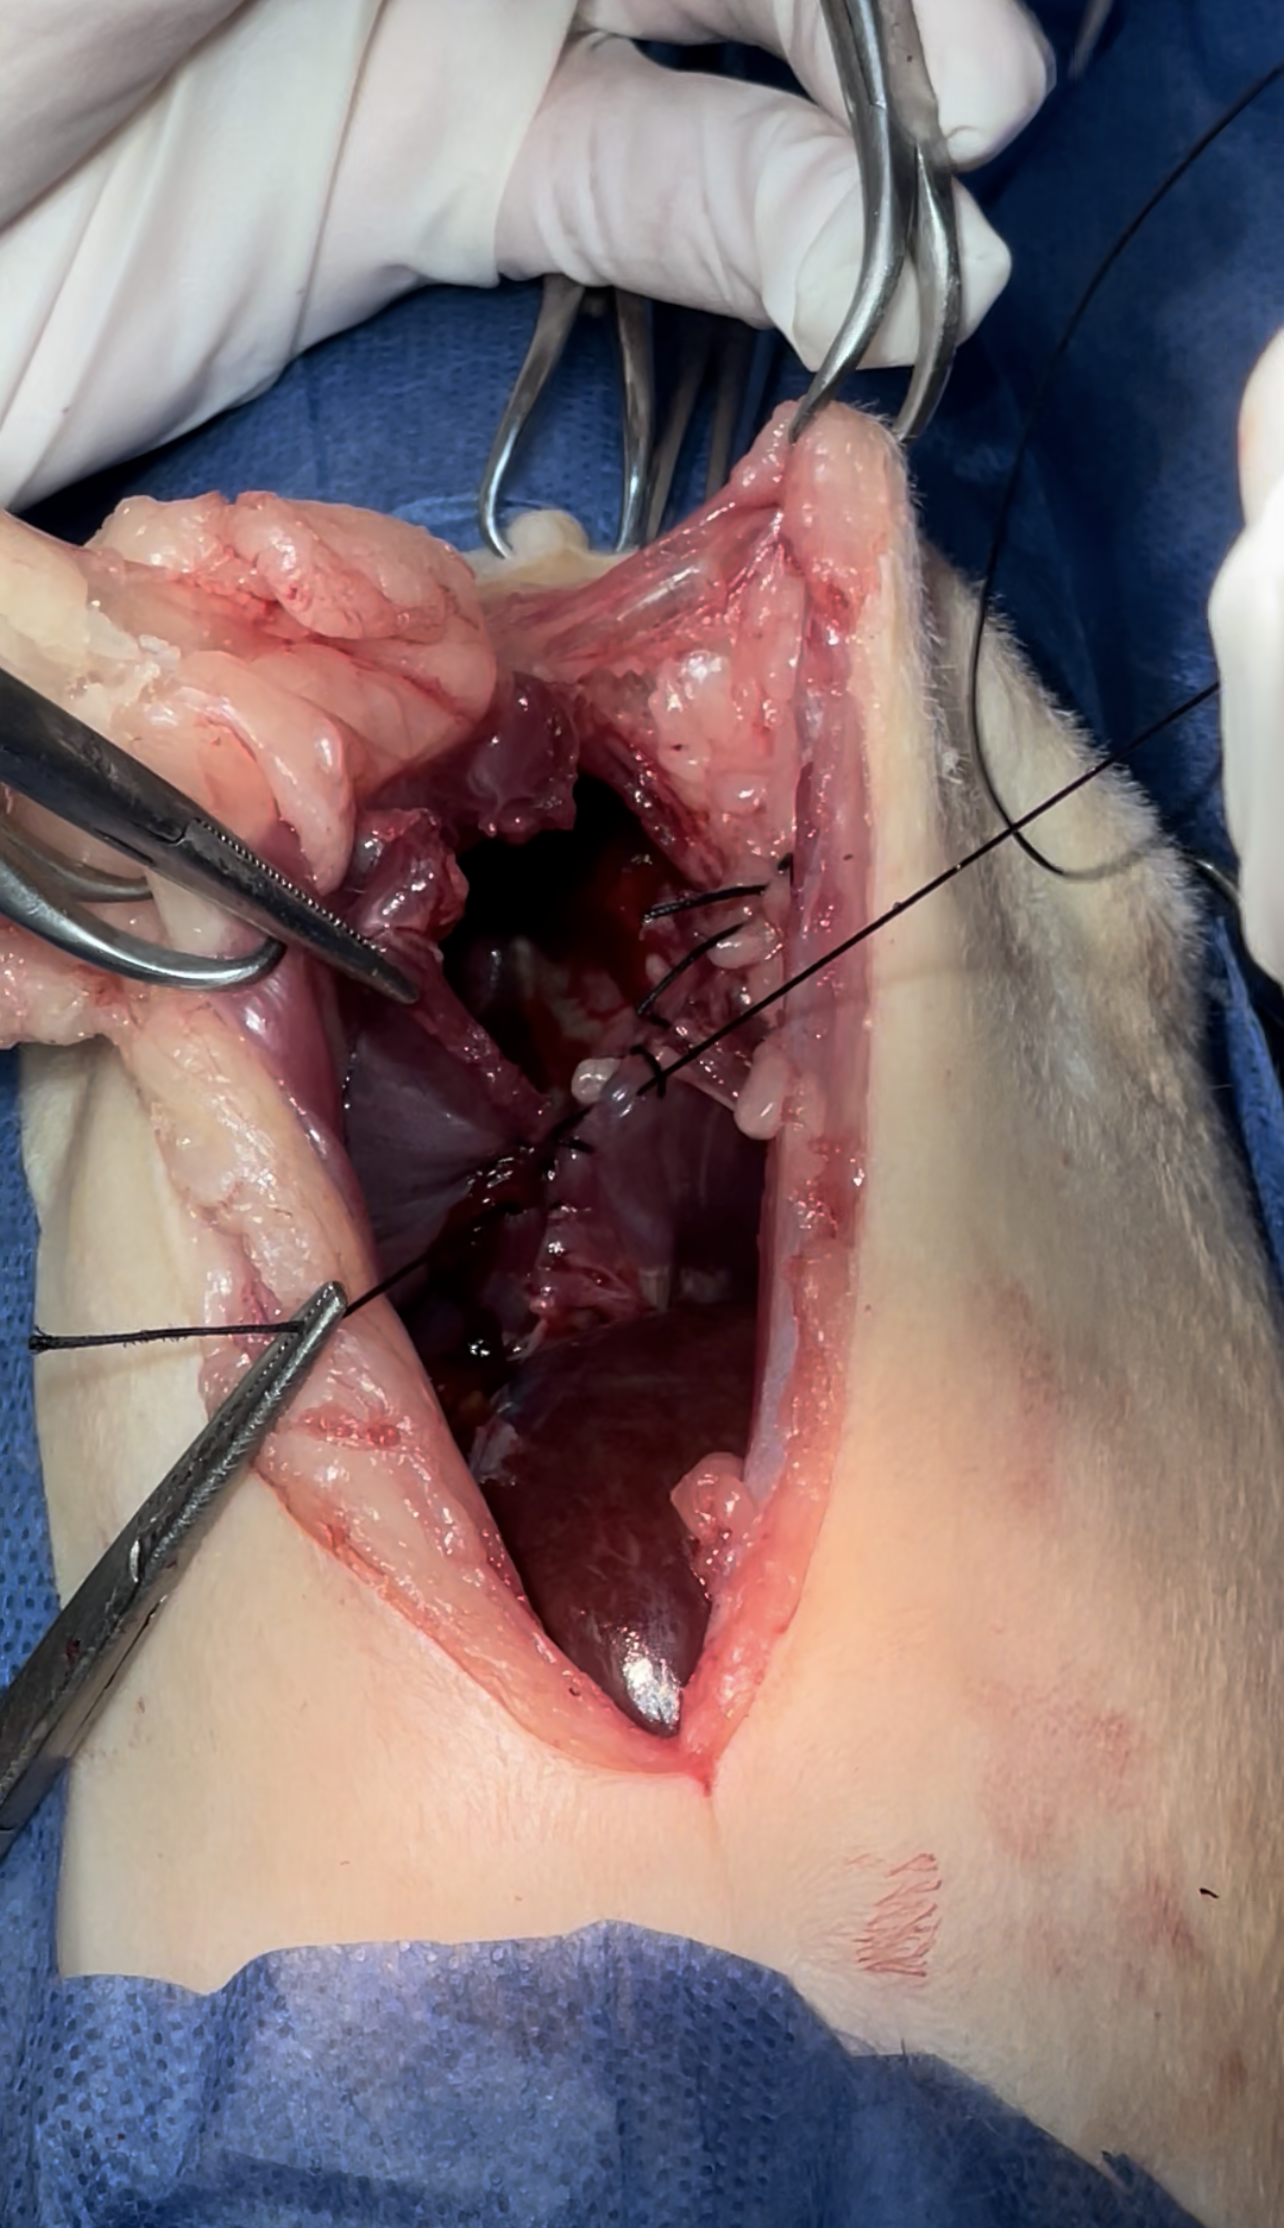

Dissection of the intraabdominal adhesive part of the live

Widening the herniation to allow organ exteriorization

Lacerations while dissection compressed with Gelfoam to minimize the parenchymal injury